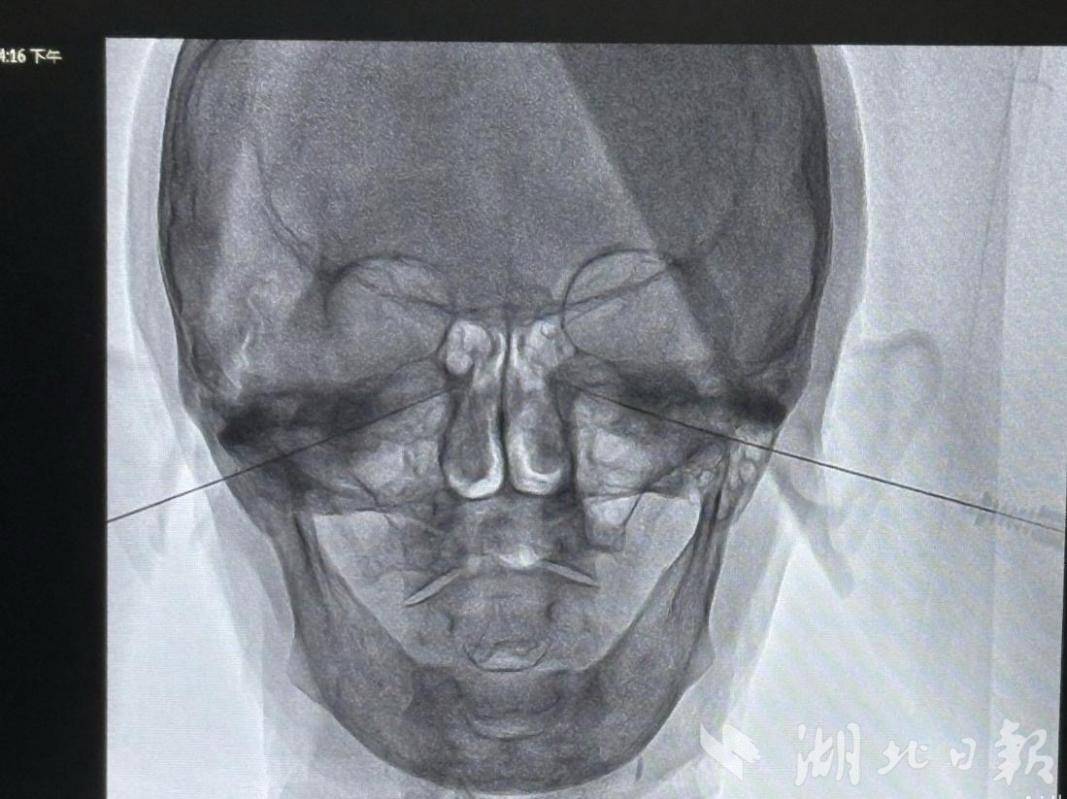

针对常规治疗无效的情况,专家团队为叶婆婆定制了微创手术方案。手术在局部麻醉下进行,借助影像学精准定位,医生用极细穿刺针抵达控制鼻腔腺体分泌的“总开关”——蝶腭神经节,通过42℃以下的温和电脉冲进行射频调控。整个手术仅耗时15分钟,患者全程清醒,面部无任何创口,观察一晚后便安全出院。